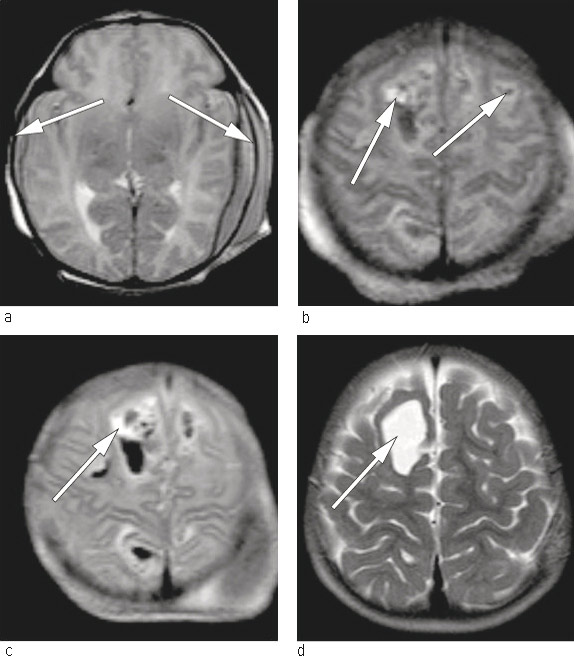

To friske, ubeslektede foreldre fikk sitt første barn etter et ukomplisert svangerskap. Fødselen skjedde ved svangerskapslengde 39 uker og to dager. Barnet ble født etter akutt keisersnitt pga. occiput posterior, langtrukket fødselsforløp og risvekkelse. Barnet var slapt og blekt ved fødselen, veide 2 740 g og fikk apgarskår 2, 6, 7 etter henholdsvis ett, fem og ti minutter. På grunn av respiratorisk besvær ble hun ventilert ved hjelp av maske og bag de første tre minuttene, deretter med Neopuff (maske-CPAP) i 15 minutter. Det ble observert multiple petekkiale hudblødninger samt hematomforandringer over caput like etter fødselen. Hematologiske prøver viste alvorlig trombocytopeni – 9 · 109 celler/l (145 – 390 · 109 celler/l). Det ble gitt bestrålt trombocyttkonsentrat fra fire tilfeldige givere (15 ml/kg), intravenøs injeksjon av polyklonalt immunglobulin (IVIg) på 0,8 g/kg samt K-vitamin peroralt. Cerebral ultralyd viste parenkymatøs blødning medialt i parietalcortex bilateralt. For nærmere kartlegging ble det utført MR caput, som avdekket bilaterale kortikale og epidurale blødninger (fig 1). Disse ble tolket som ferske. Nevrokirurg anbefalte videre observasjon og konservativ behandling.

Etter utskrivning ble barnet fulgt med blodprøver, først hver måned og deretter annenhver måned i et halvt år. Trombocyttverdiene lå hele tiden innenfor normalområdet (326 – 402 · 109 celler/l). MR caput ble gjentatt ved én og 15 måneders alder (fig 1). Barnet har senere vist normal psykomotorisk utvikling og er i dag en frisk femåring.

For barn nummer én var fødselsforløpet frem til operativ forløsning langtrukkent. Den intrakraniale blødningen var fersk på fødselstidspunktet (fig 1). Man kan stille spørsmålet om hvorvidt dette kunne ha vært unngått dersom man hadde kjent til morens trombocyttype og antistoffnivå i svangerskapet og utført keisersnitt 2 – 3 uker før termin med forlikelige trombocytter i beredskap til barnet.